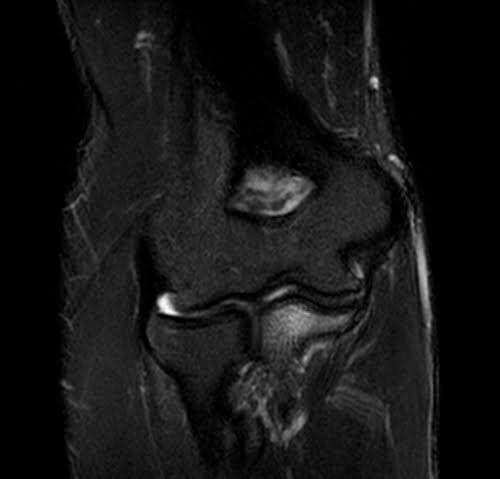

mri elbow coronal stir image 2 - MRI